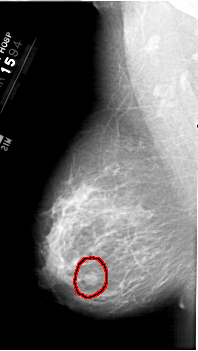

A_1387_1.LEFT_CC

FILE: A_1387_1.LEFT_CC.OVERLAY

TOTAL_ABNORMALITIES 1

ABNORMALITY 1

LESION_TYPE MASS SHAPE ROUND MARGINS CIRCUMSCRIBED

ASSESSMENT 4

SUBTLETY 4

PATHOLOGY BENIGN

TOTAL_OUTLINES 1

BOUNDARY